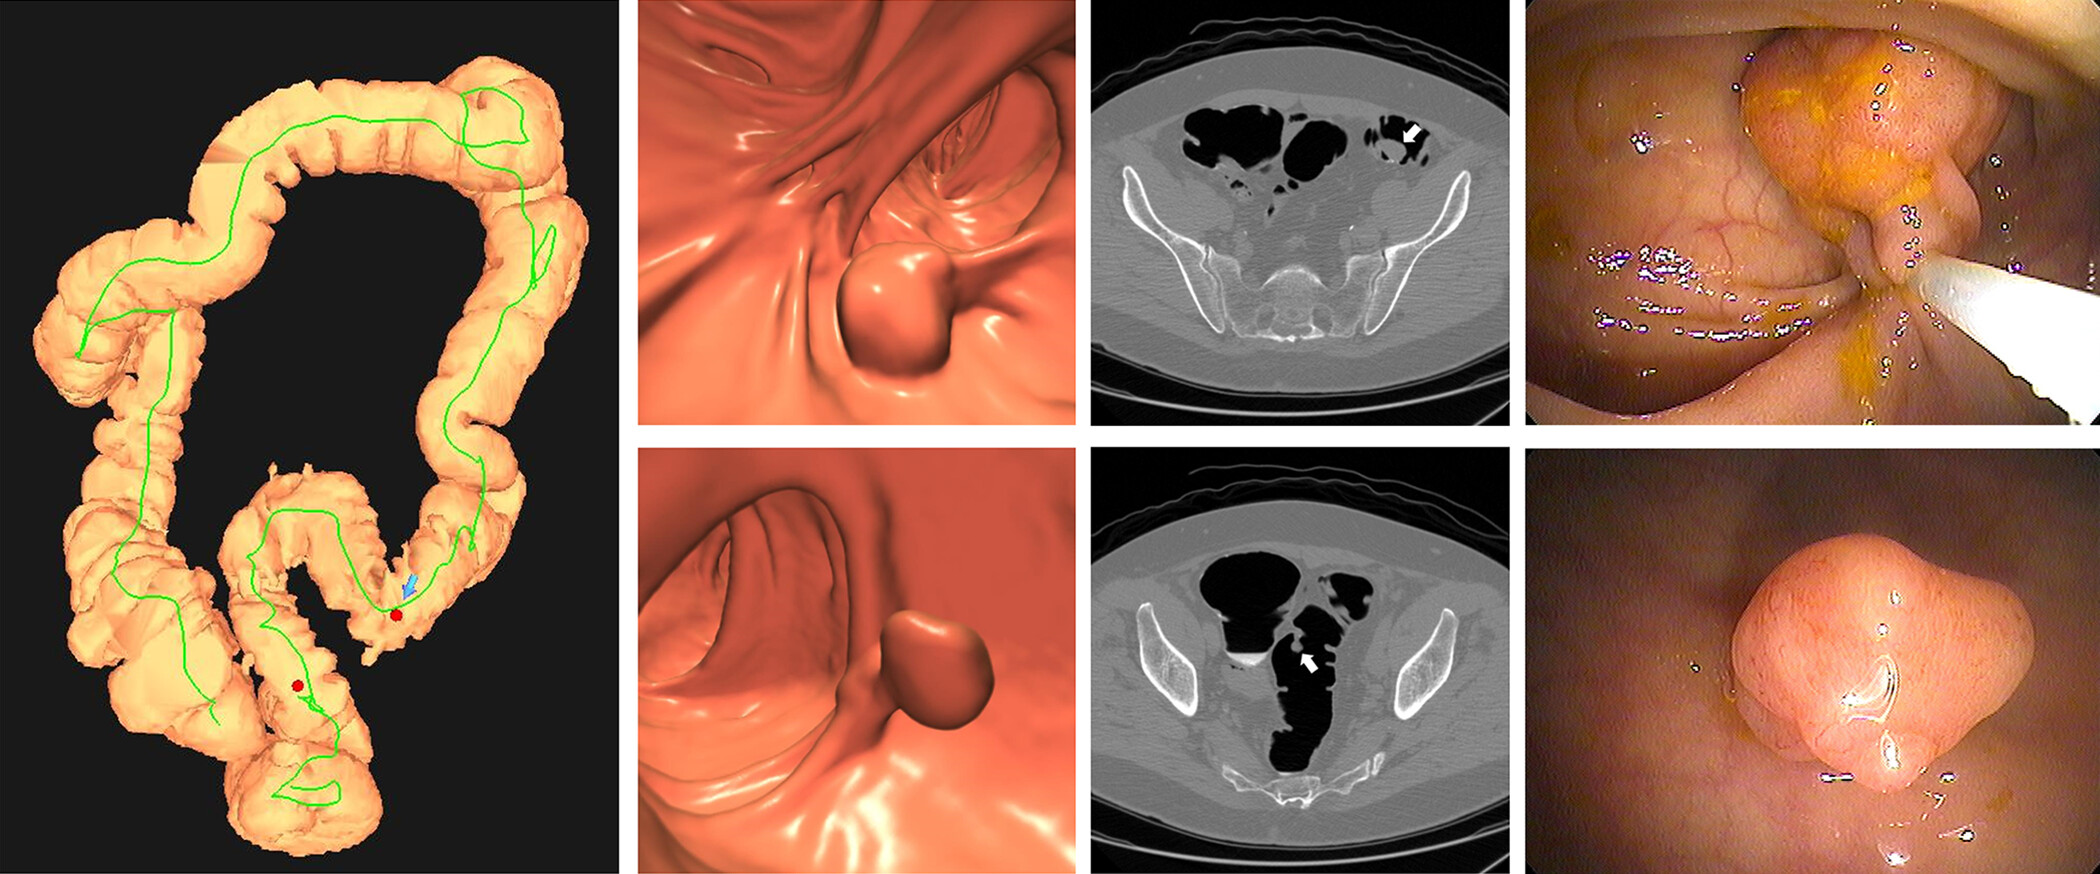

Unlike colonoscopy, there’s no risk of bleeding or perforating the colon associated with CTC. Instead of a scope, computed tomography scans are used to create 3D images of a patient’s colon from different angles. Patients are able to resume normal activities and even drive themselves home following the procedure. If polyps are detected, same-day GI Clinic services are available for polypectomies.

This summer, Drs. Pickhardt and Kim published “CT Colonography for Colorectal Cancer Screening and Prevention: 20-Year Programmatic Experience at a U.S. Academic Medical Center” in the American Journal of Roentgenology (AJR). Insights support CTC as a safe, noninvasive way to detect and prevent CRC. Dr. Pickhardt discussed the study with AJR Editor in Chief Andrew Rosenkrantz, MD.